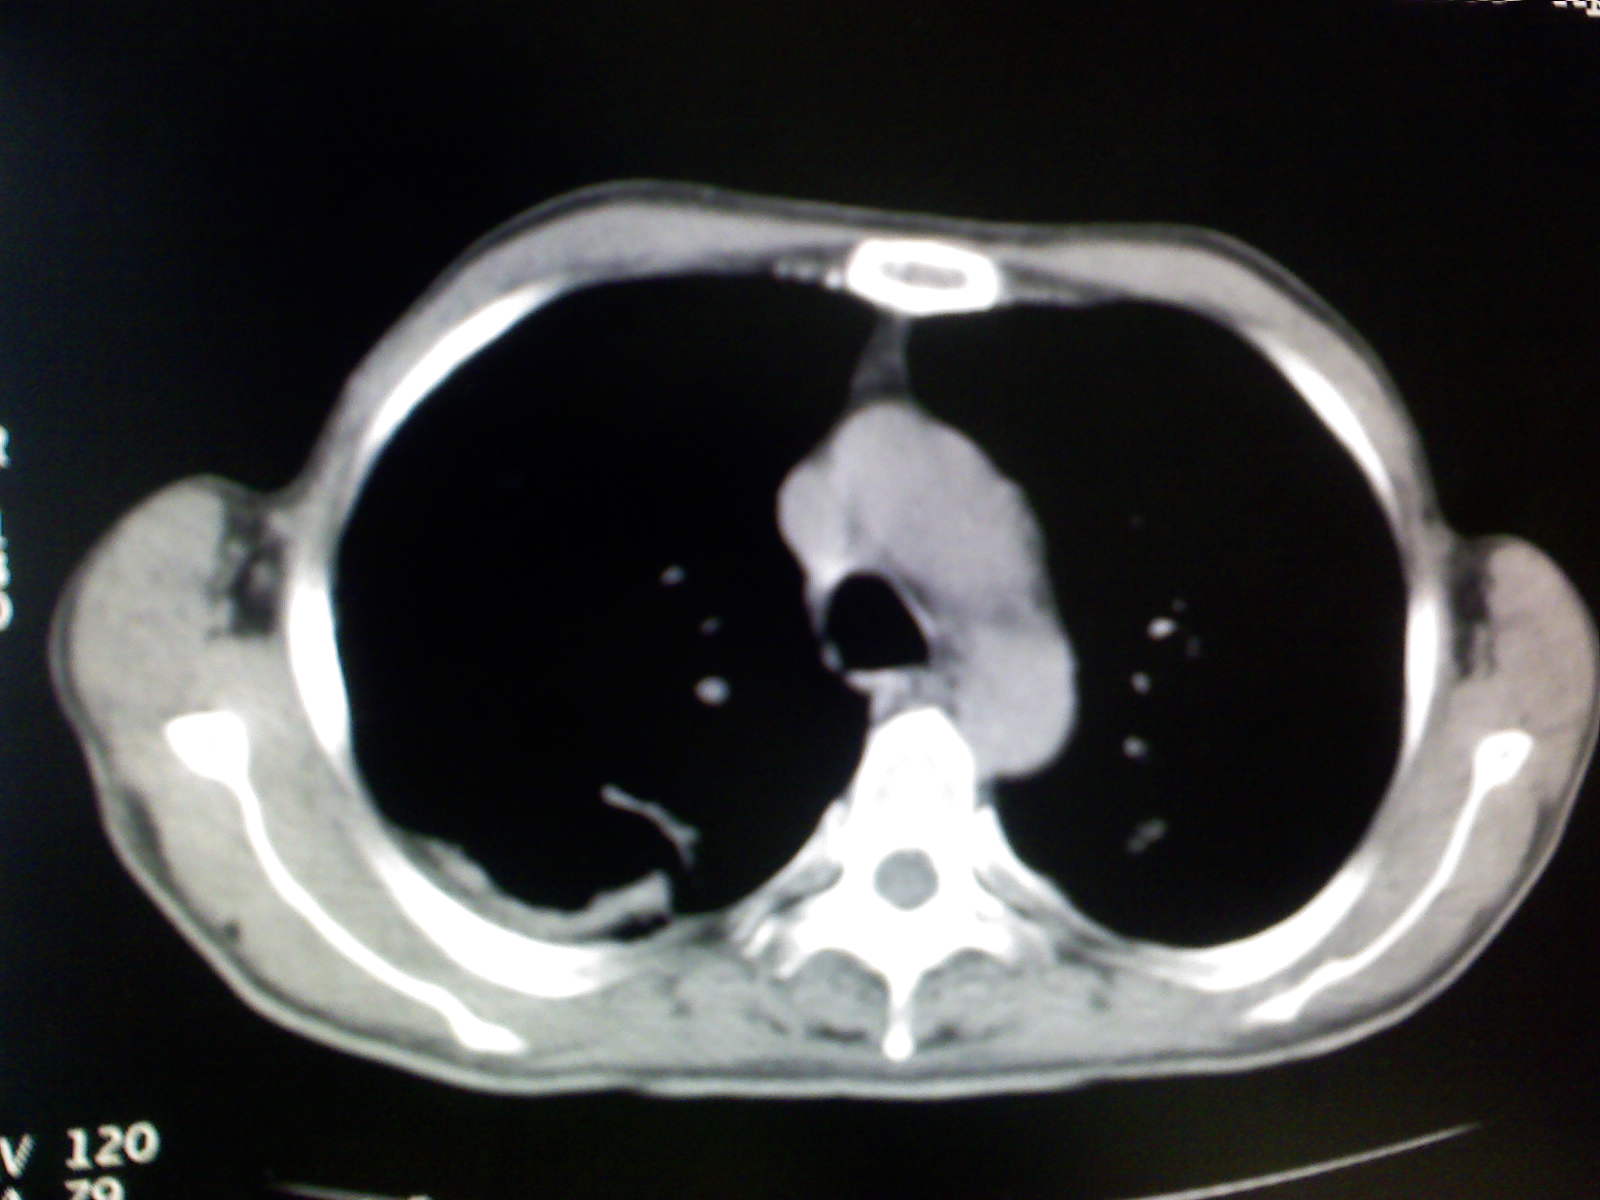

以下是引用卜一在2009-4-11 15:50:00的发言:[br]双肺继发性肺结核伴空洞形成,不排除合并霉菌感染!(病灶呈多形态 多特征 散在分布)。另:合并支气管扩张征伴感染!

以下是引用康鹏在2009-4-11 16:30:00的发言:[br]双肺继发性肺结核伴空洞形成合并感染[br]支气管扩张合并感染